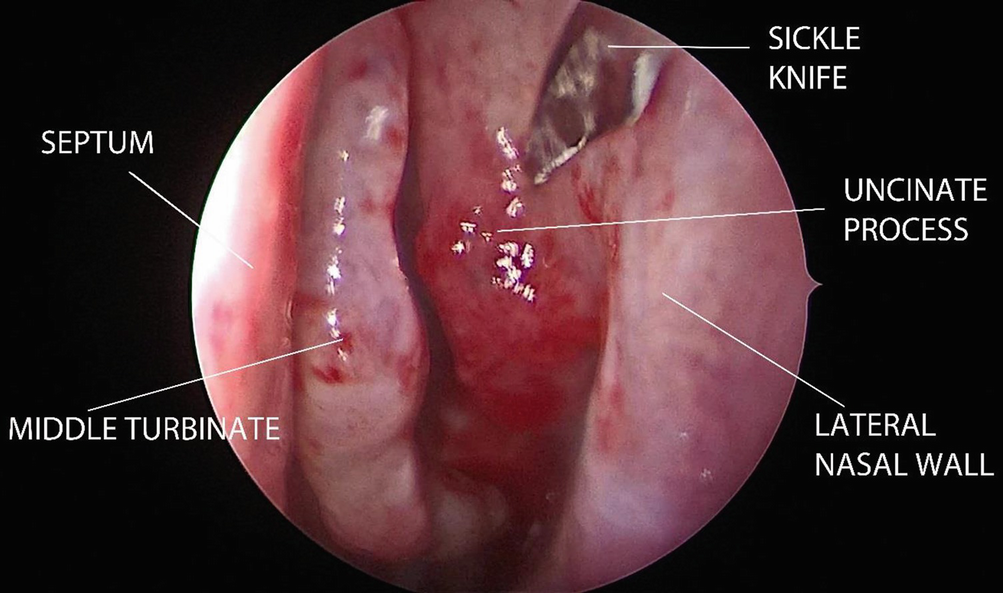

By using a 0 degree Hopkins telescope, the anterior attachment of the uncinate process is incised with a sickle knife and medialised to reveal the infundibulum. The upper and lower attachments of the uncinate process are cut with a straight Blakesley forceps, and it is removed with a twisting motion (Fig. 12.2).

../images/481431_1_En_12_Chapter/481431_1_En_12_Fig2_HTML.png

Fig. 12.2

The first step in FESS is the uncinectomy